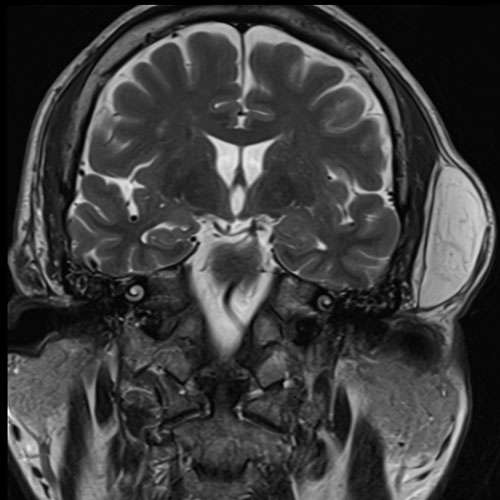

手術前(MRI)

MRIを取ると、明らかに大きな脂肪腫を認めます。

頭の横には大事な血管:浅側頭動脈などがあるので、こちらを注意しなければいけません。